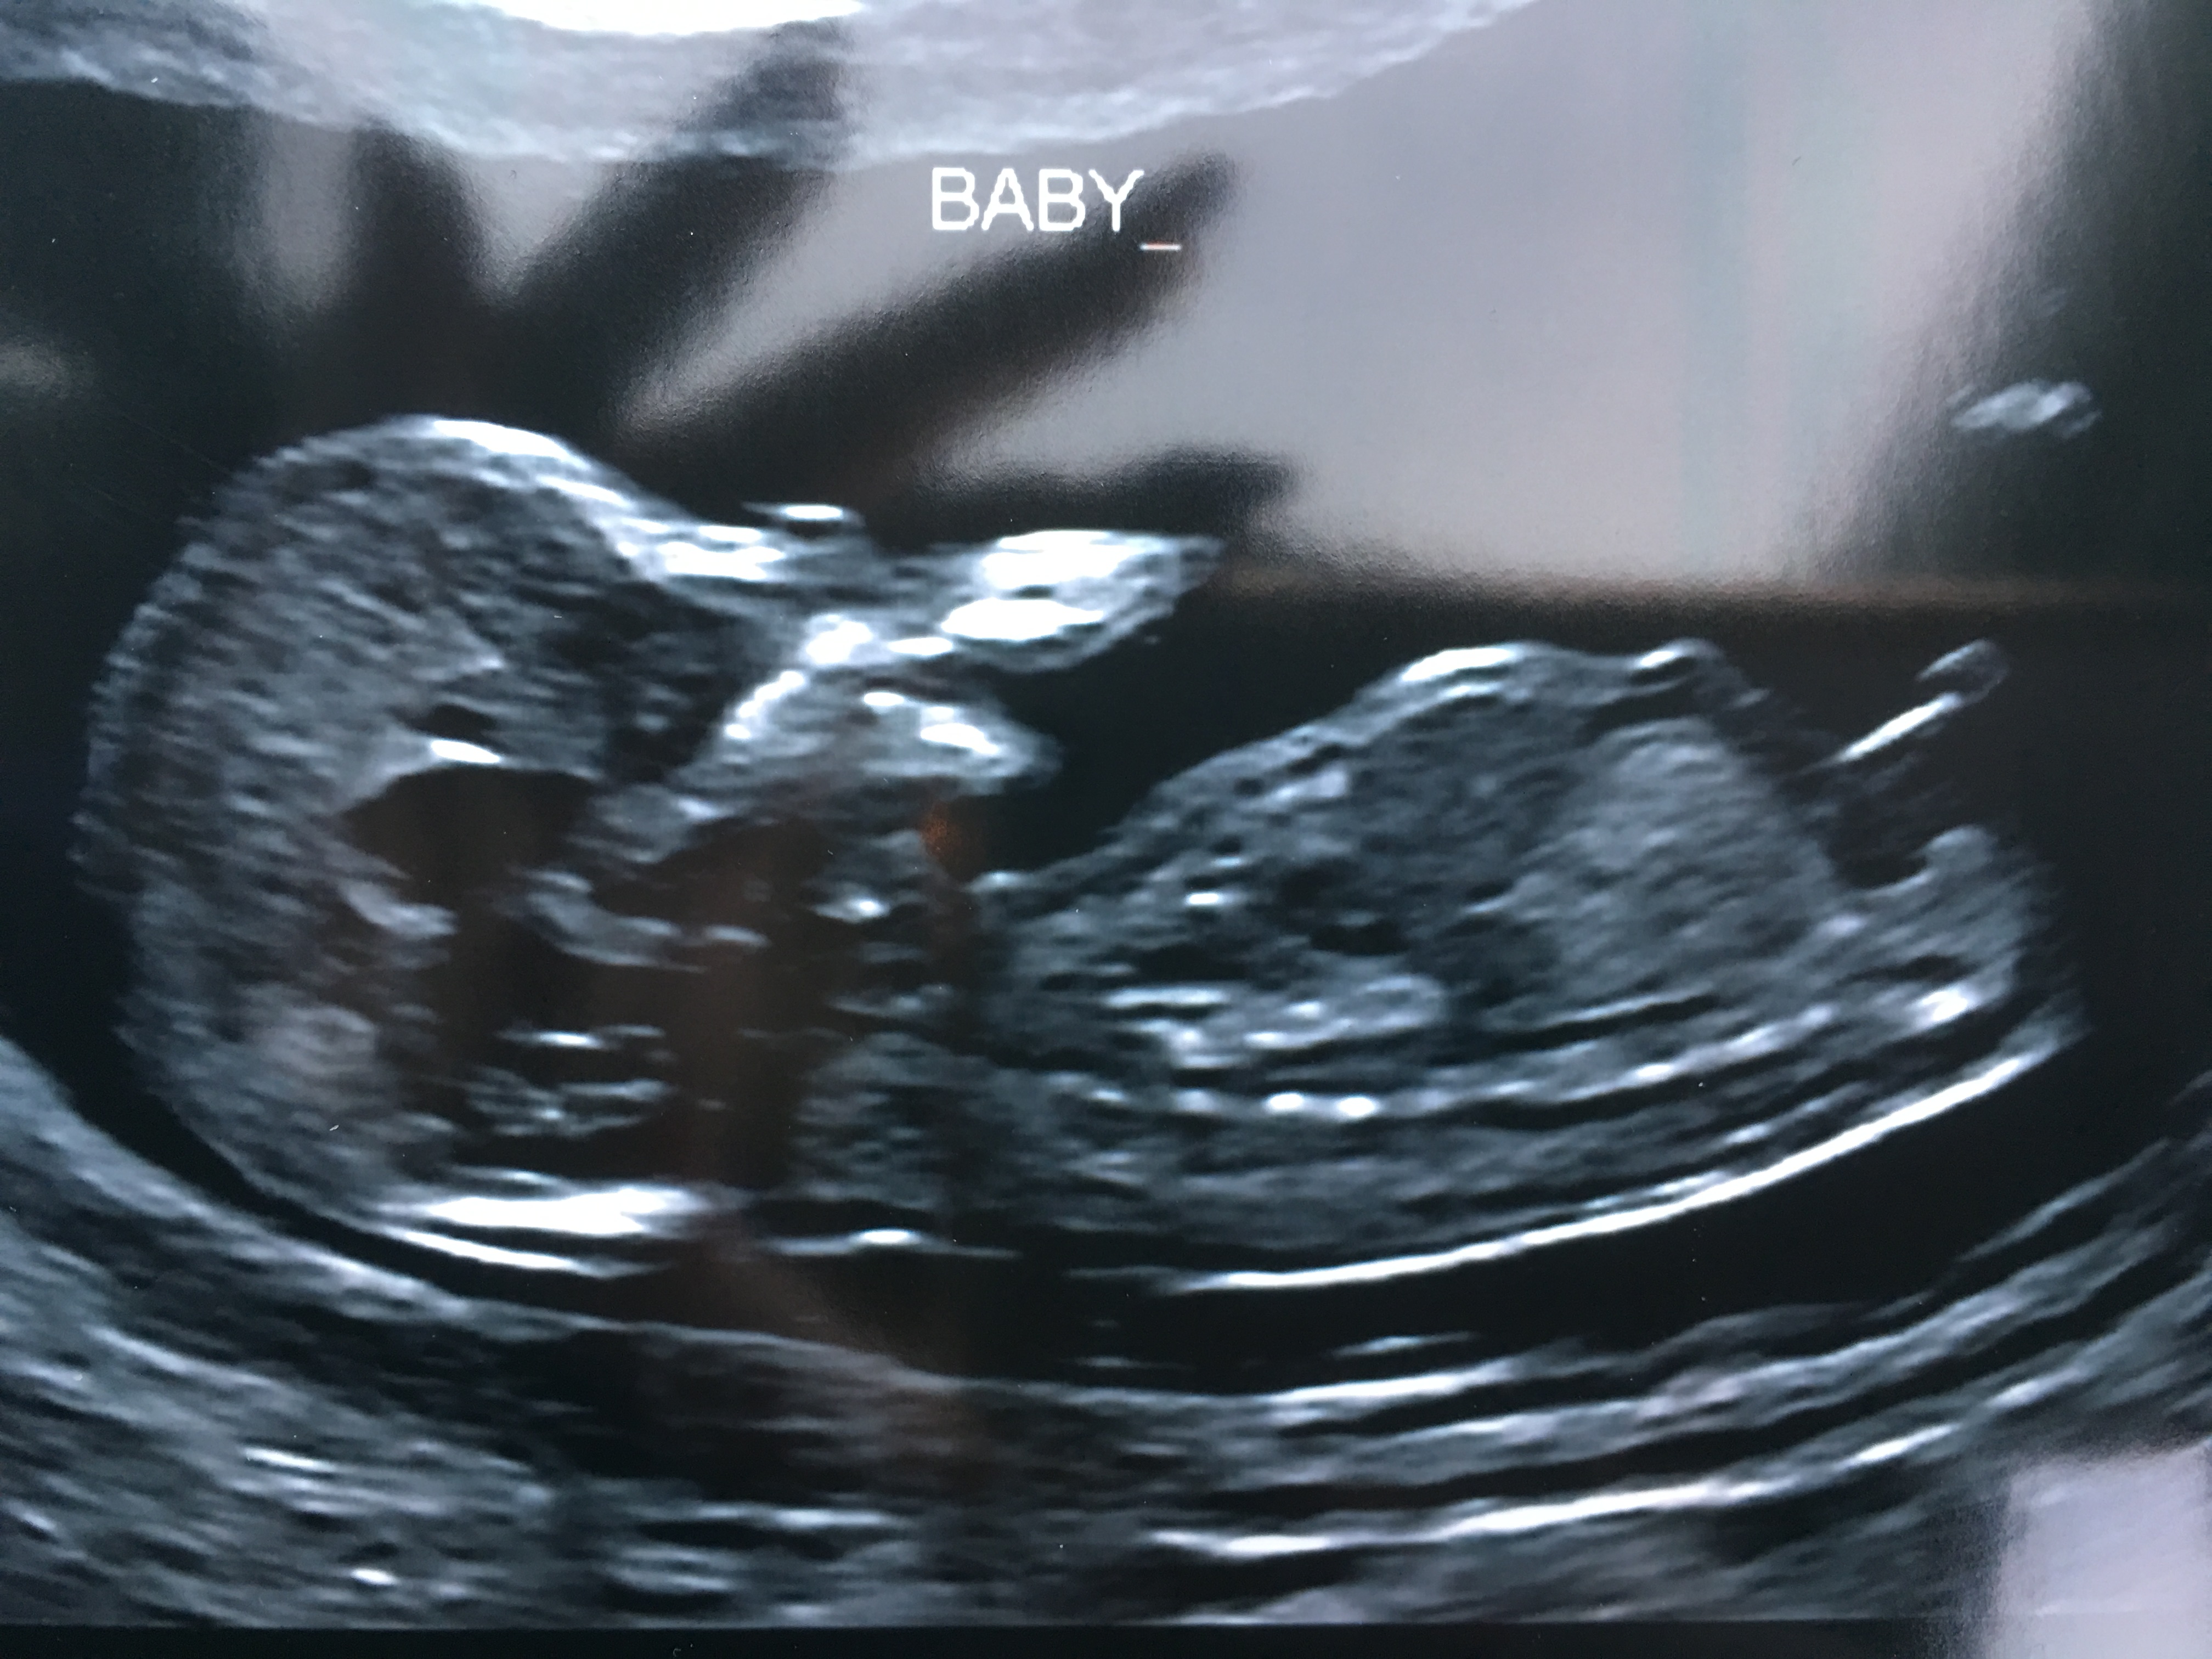

This is my ultrasound from yesterday at 13w2d. Can anyone guess if I will have a boy or a girl!! Thank you 😊 Attachment 34434

Tricky nub, more pics?

I think boy? At 13w2d, that's a pretty long, angled nub let alone with the "stacking" that seems to be boyish. I don't think that's cord, but if that's nub, I'd say boy. Your potty shot is what throws me, but that's probably why potty shots that early are so inconclusive!

I say boy. But not sure.